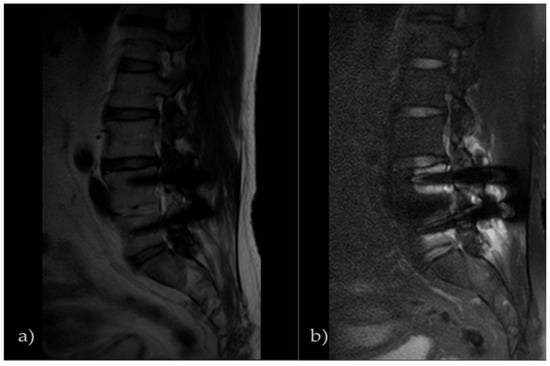

2.1. Subjects

3.1. SNR Result of Pig L-Spine Phantom

3.2. SNR Result of Transplant Patients

3.3. Histogram Measurement Results